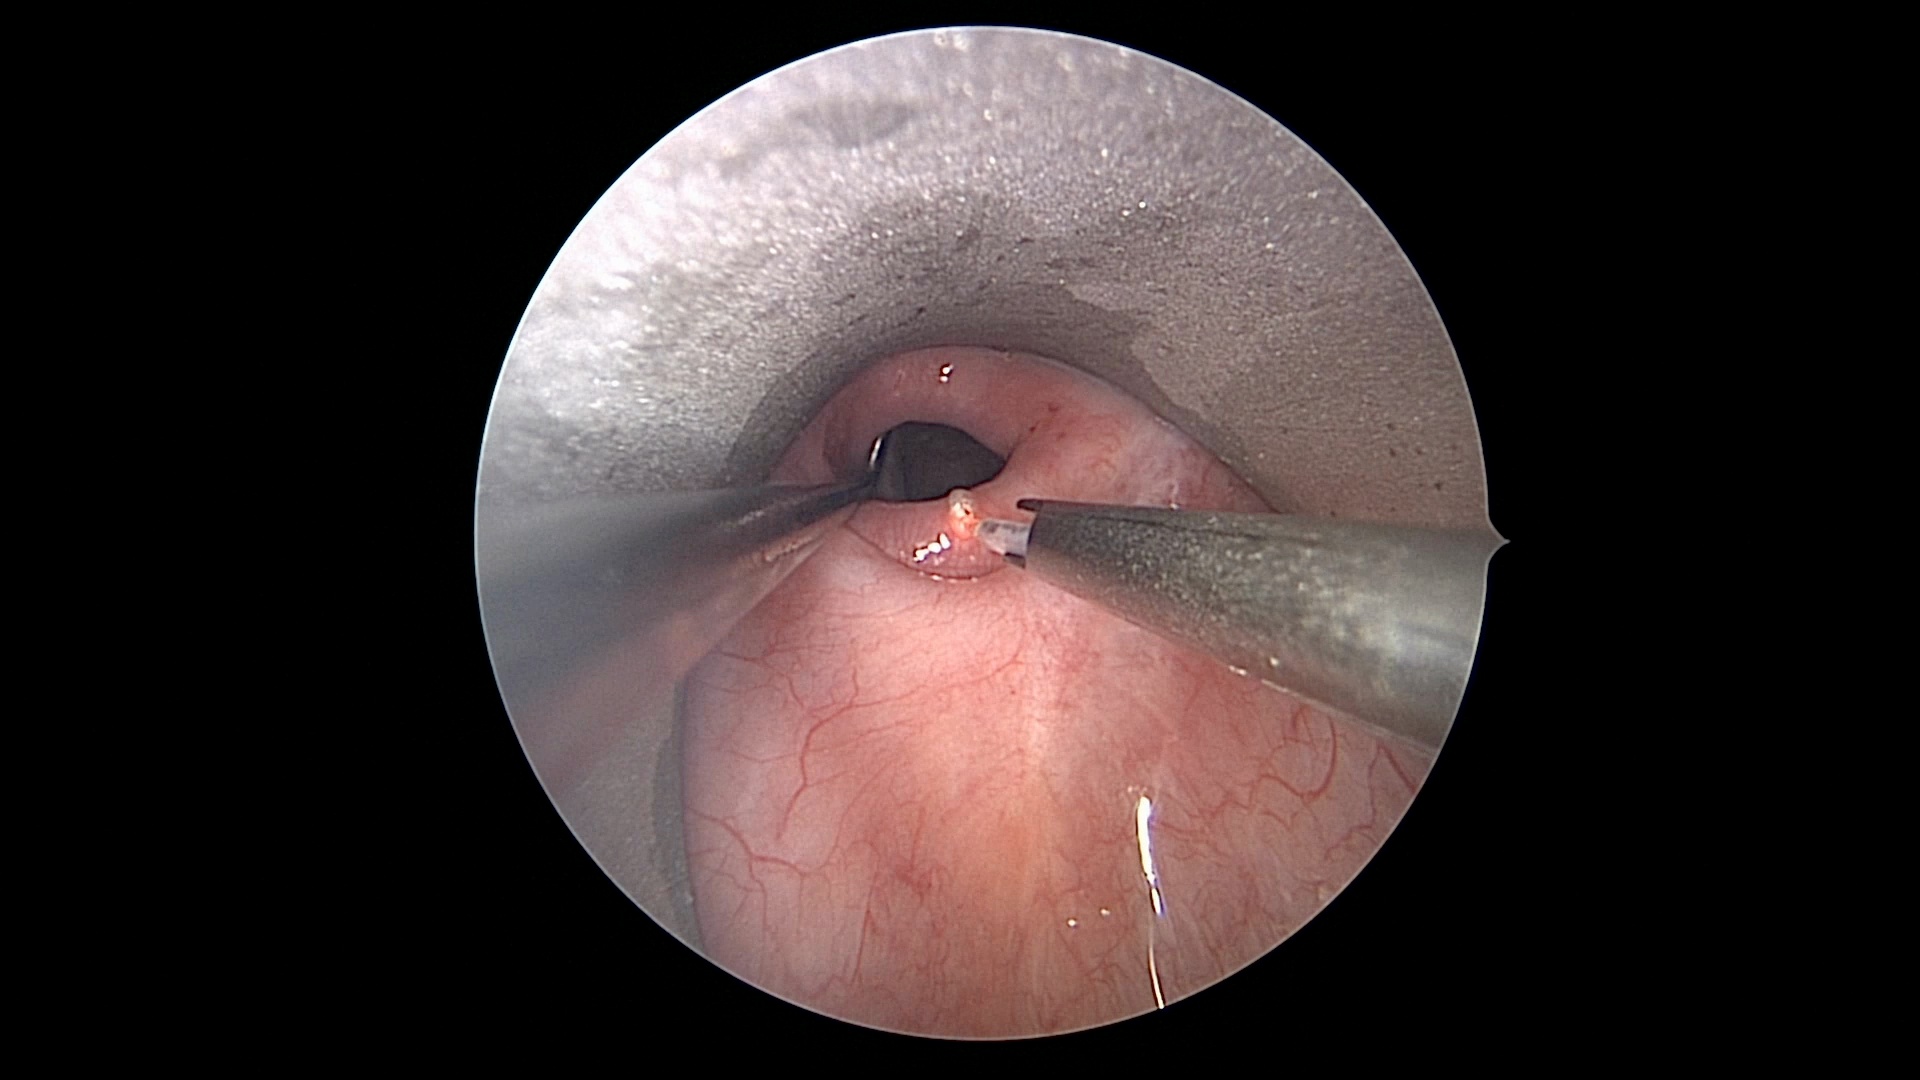

Watch the Full VideoIntroduction: Cricopharyngeal dysfunction (CPD) is a spectrum disorder encompassing multiple entities that ultimately result in dysphagia as a result of disruption of the normal anatomy or physiology of upper esophageal sphincter. It is a known and well described cause of dysphagia in adults, however, it’s role in pediatric dysphagia is less clear and limited to mostly small case series.1 Despite it’s relatively low prevalence, the complex pediatric otolaryngologist must be aware of this entity and it’s management. We discuss a complex case of CPD with an associated cricopharyngeal bar and pharyngeal diverticulum, as well as our successful endoscopic surgical approach highlighting the principles of CPD management in children. Case Presentation: We present a 21 month of female with a history of DiGeorge Syndrome and oropharyngeal dysphagia. Despite appropriate conservative measures including feeding therapy and diet thickening modification, as well as attempted Botox injection, the patient continued to demonstrate dysphagia. It was also noted on her swallow study that she had a posteriorly based pharyngeal diverticulum that potentially served as an aspiration reservoir. The decision was made to proceed with endoscopic cricopharyngeal division and diverticulum marsupialization. Technique: With the patient intubated, a Lindholm laryngoscope was placed posteriorly into the hypopharynx, elevating the larynx and allowing visualization of the upper esophageal sphincter and isolation of the cricopharyngeal bar. A non- contact CO2 laser fiber at 2W continuous spray was then used to divide the cricopharyngeal bar layer by layer making sure to isolate the muscle and not create a pharyngotomy. Standard laser safety precautions were followed. Tension was maintained using a right-angle hook allowing for optimal laser division. This was continued until the entirety of the bar was divided. At this point, the posterior pharyngeal diverticulum was identified. Again, with the use of a right angle probe for traction and depth assessment, The anterior wall of the diverticulum was divided. This was continued until the diverticulum was fully marsupialized and in continuity with the posterior pharyngeal wall into the esophageal inlet. Post operatively the patient was extubated and observed overnight in the hospital Swallow study three weeks later demonstrated normalization of the flow of bolus through the UES as well as resolution of the previously seen diverticulum. Conclusion: Cricopharyngeal Dysfunction (CPD) is an uncommon but recognized cause of pediatric dysphagia with multiple treatment options of varying success. Endoscopic CO2 laser division is a viable and effective treatment option for this condition.